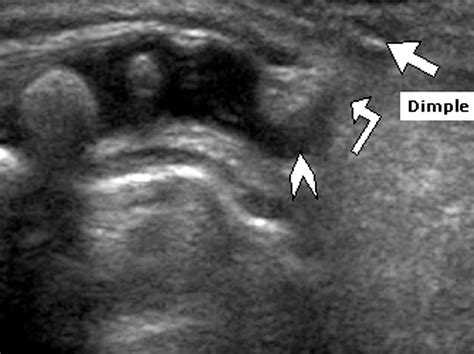

• Imaging Studies: Ultrasound, MRI, or CT scans to visualize the spinal cord and surrounding structures.

• sacral dimple newborn ultrasound